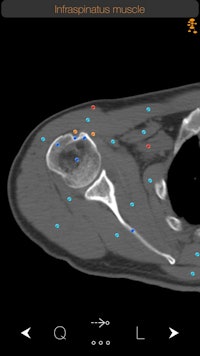

In this Mobile App Spotlight, we're taking a look at CT Anatomy, an iOS app that offers a cross-sectional guide of normal anatomy as seen on CT. It includes more than 350 axial CT views with anatomy, as well as more than 700 anatomical structures along with descriptions, according to developer iCat Medical Software, a U.K.-based mobile app firm.

CT Anatomy helps educate the user on normal human anatomy as seen on the CT. By learning normal CT anatomy, you are taking the first step toward correct diagnosis.

A CT Anatomy app can't deviate much from its intended purpose, which is to demonstrate the anatomy of the human body. It has to be complete and comprehensive. However, sometimes a single anatomical name does not give you the whole picture of that structure. So we have taken this one step further by including information in a very easy and nonobstructive way about the anatomical structure you are searching for.

Another feature that I personally like a lot is what we call FollowMe mode. Looking at a 2D image and trying to figure out where an anatomical structure comes from or goes to is sometimes difficult. With CT Anatomy, the user can follow an anatomical structure through its course and understand better its relationship with other adjacent structures.